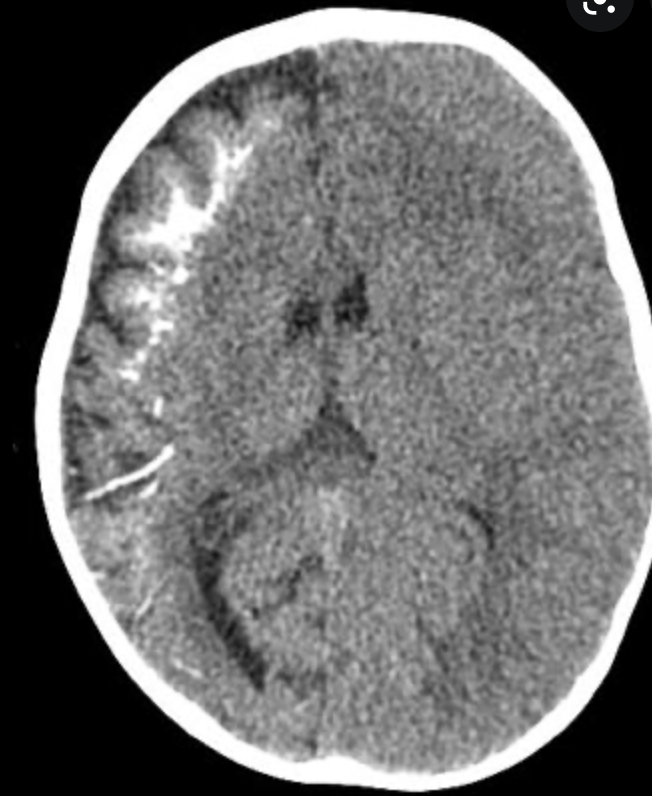

Brain and cerebrovascular malformations are common 6,8:

persistent cavum septi pellucidi and/or cavum vergae (19-33%)

aberrant cortical veins (25%)

polymicrogyria or cortical dysplasia (17%)

white matter hyperintensities (10%)

hypoplastic internal carotid artery (8%)

brain volume loss, most pronounced in the cerebellum (see hypoplastic cerebellum) 9

What syndrome is this finding associated with

http://www.ajnr.org/content/35/11/2186

Di George

CATCH22

C - cavum septum pelucidum, cleft palate,

A - Abnormal Facies (hypertelorism, low set ears, short philtrum, among others)

T - Trunchus ateriosus, Thymic Hypoplasia

C - cardiac anomalies

H - hearing problems. Middle ear malformations. Hypoparathyroidism

22 - Microdeletion of 22q11.2